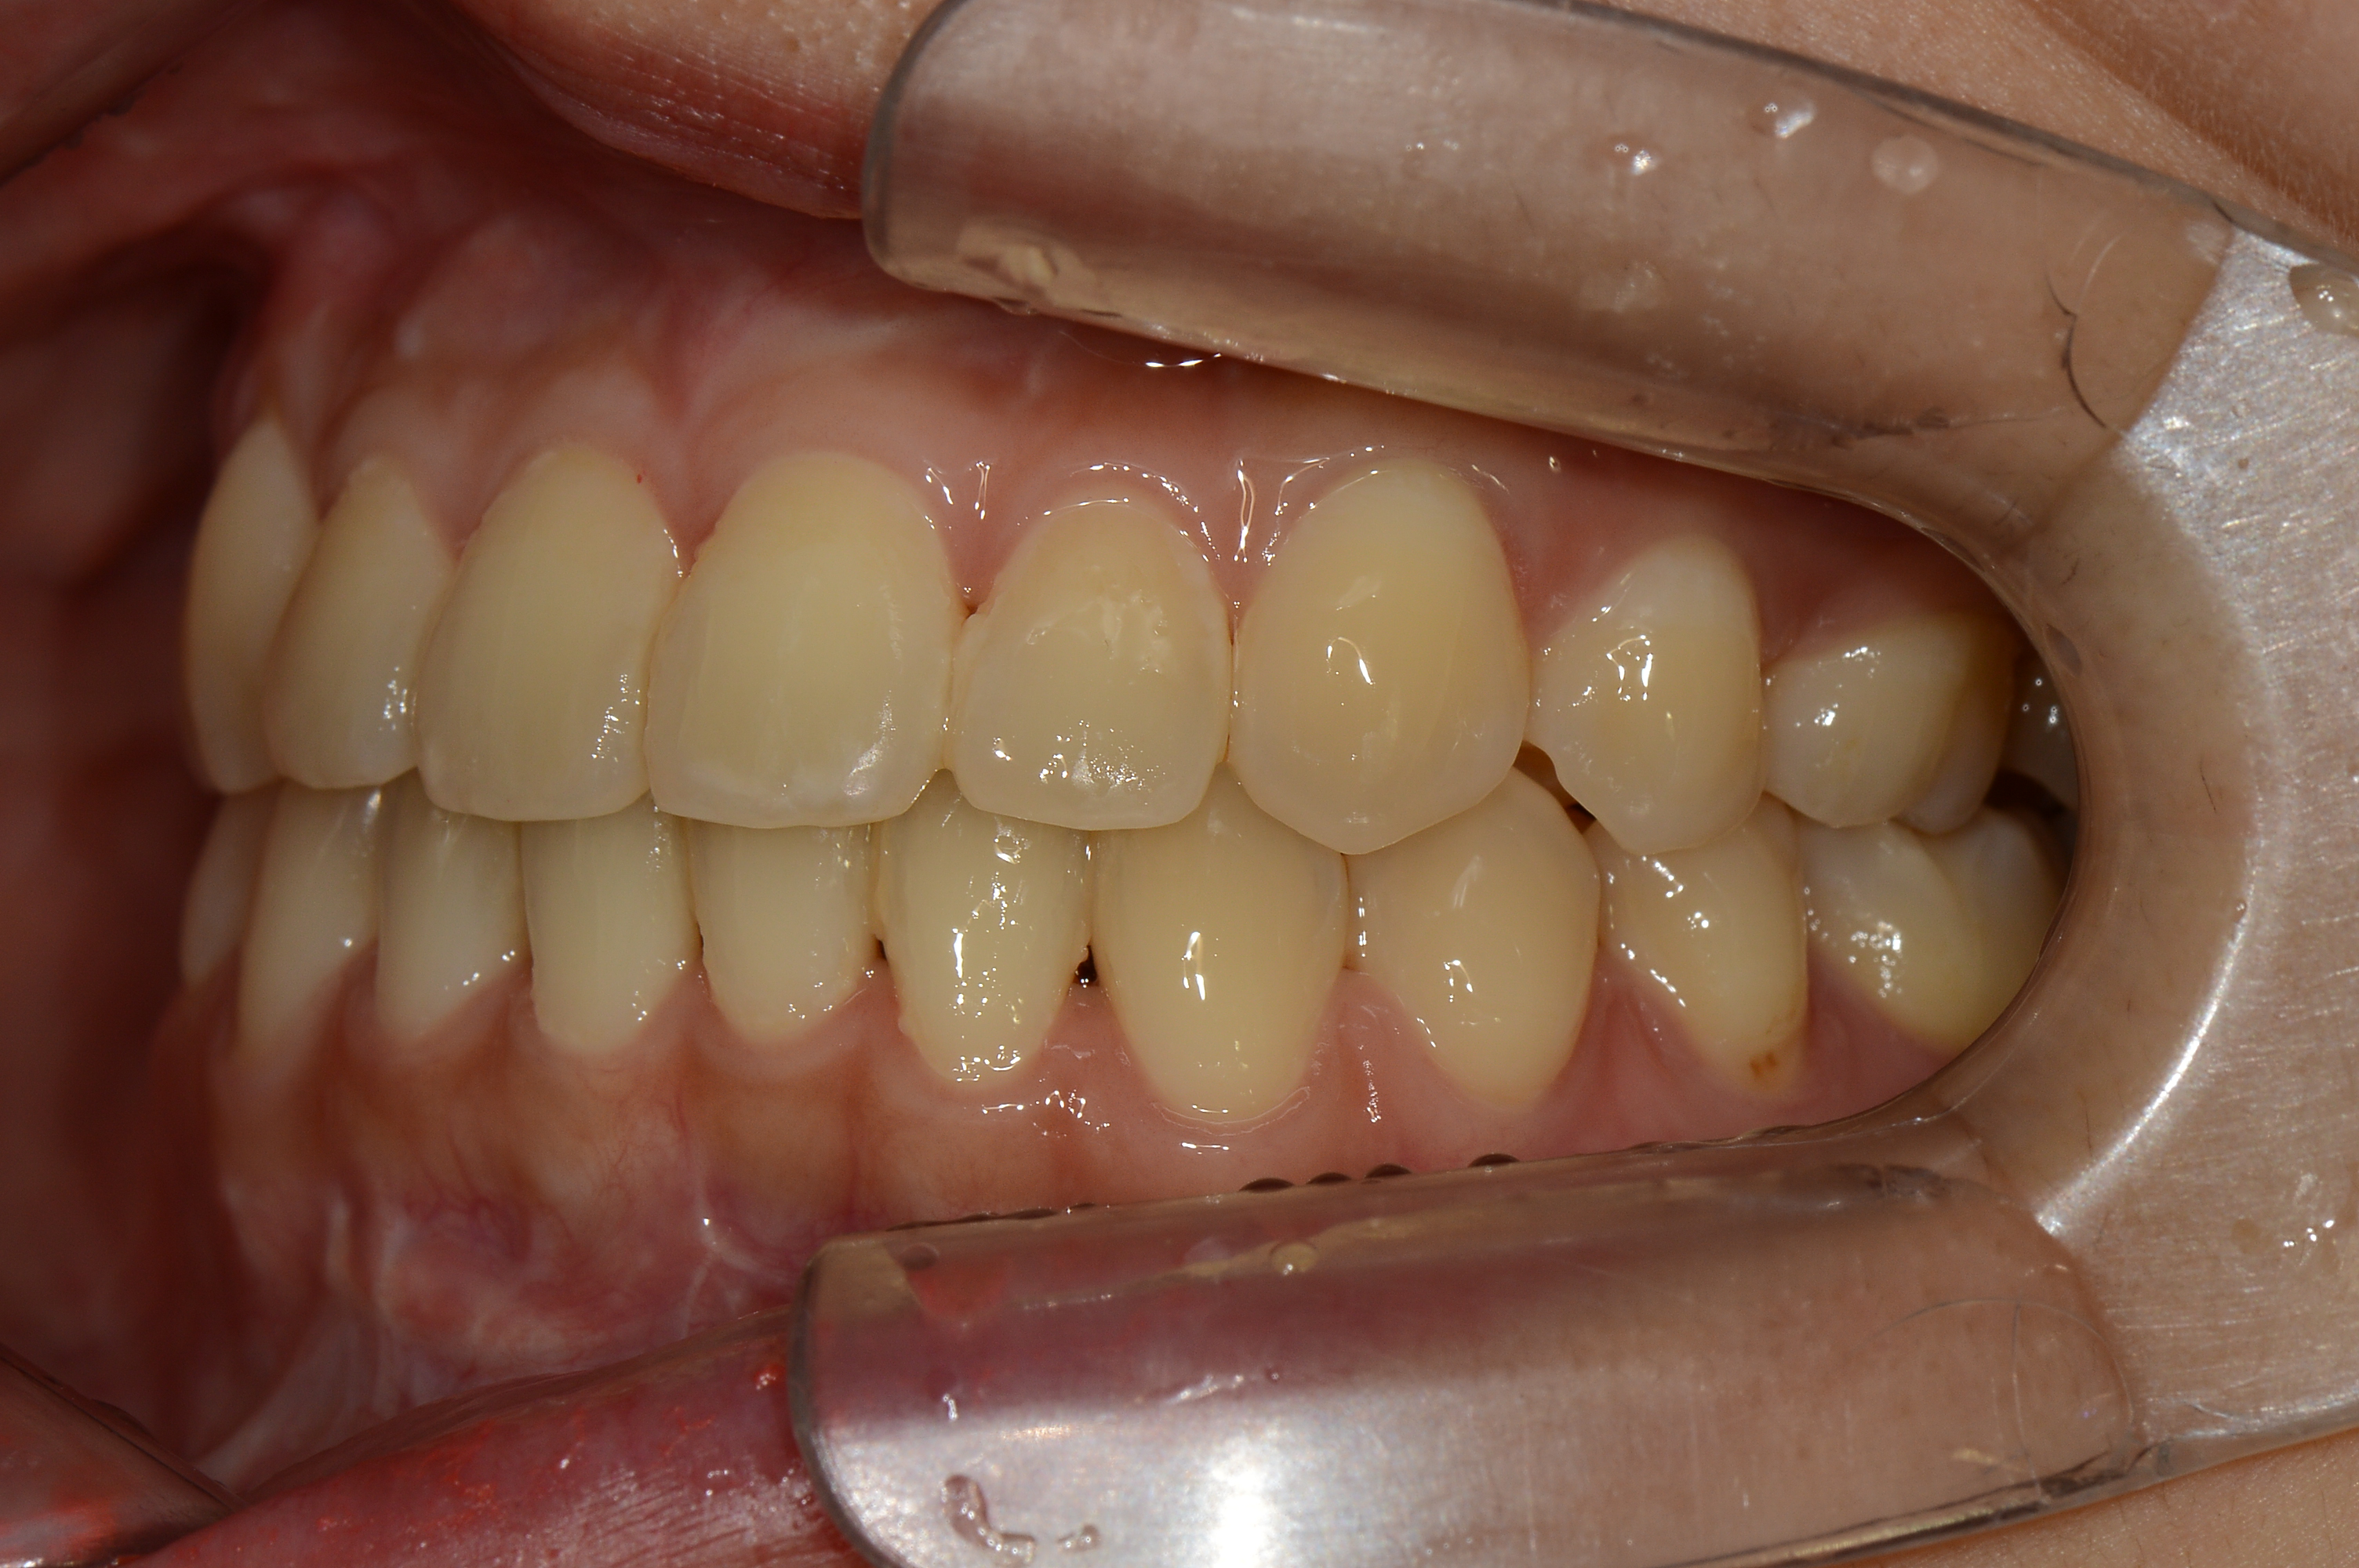

치료 후 사진입니다.